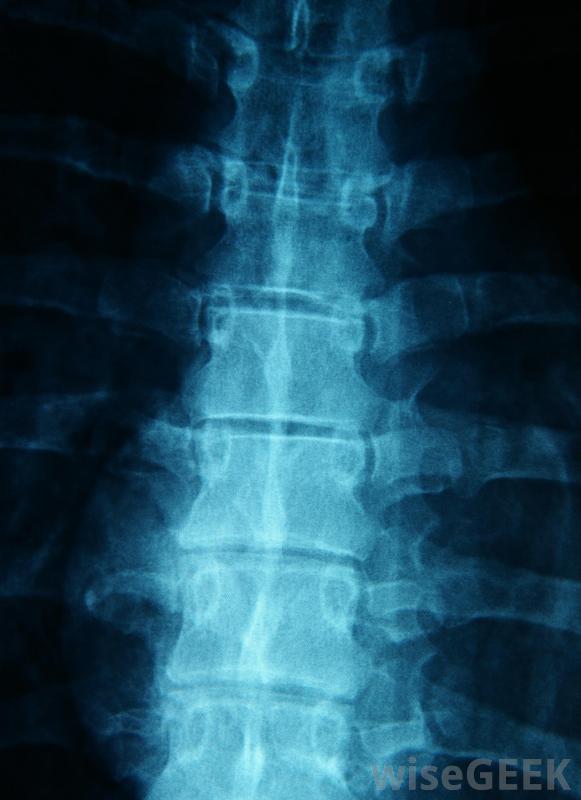

什么是硬膜外腔間注射(Interlaminar Epidural Injection)?

椎板間硬膜外注射是一種將類固醇輸送到脊神經根部的藥物。這類硬膜外注射有三種不同的類型:頸段硬膜外注射、腰段硬膜外注射和胸段硬膜外腰段注射。注入脊神經根的類固醇有助于戰斗與背部、腿部、手臂和肩部相關的炎癥和疼痛。層間硬膜外注射可用于減輕分娩和分娩過程中的疼痛受傷的椎間盤或骨刺會導致脊髓神經發炎。這通常會導致高度的疼痛和不適,需要硬膜外類固醇注射來開始愈合過程。在層間硬膜外注射中,類固醇作用于神經根,也可能引發一個解毒過程,在這個過程中,受影響區域的炎性蛋白被沖出體外。注射還可顯著減輕炎癥和疼痛,從而支持身體自然愈合過程的開始頸部疼痛可以通過使用頸段硬膜外注射來減輕硬膜外注射通過進入包裹脊神經的硬腦膜周圍區域起作用所有從脊椎到手臂、腿部和胸部的神經都會經過這個區域。注射時,針頭直接插入隔膜,將類固醇注射到狹小的空間。硬膜外腔間注射可幫助治療臀部疼痛在層間硬膜外注射過程中,靜脈注射首先輸送麻醉劑,這樣身體就可以放松注射,病人被放在胃部的x光臺上,注射區域周圍的皮膚被消毒。此時,另一種麻醉劑被注射到注射區域,進一步放松神經末梢,使整個過程更加痛苦。一種稱為透視的x光片允許醫生將針頭精確地引導到脊椎的正確位置。接下來,進行兩次注射:一種是一種特殊的染料,可以確保類固醇的靶點正確的區域,另一個是類固醇本身,與另一種麻醉劑聯合使用,以保持患者的舒適性。腰麻硬膜外類固醇注射最常用于坐骨神經疼痛患者椎體間硬膜外注射通常用于治療脊柱三個部位之一的炎癥。在頸段硬膜外注射中,類固醇可以減輕頸、肩和臂的疼痛腰段硬膜外注射會影響下背部、臀部和臀部的疼痛,以及腿部的不適。對于胸段硬膜外麻醉,這種藥物可以抑制上背部、肋骨的炎癥,在某些情況下,腹部。大約50%的患者報告在接受層間硬膜外注射后,患處疼痛明顯減輕。一種稱為透視的X光片可以幫助醫生找到脊椎的精確位置硬膜外腔間注射可以使身體的某些部位因疼痛而麻木,例如在分娩或手術時層間硬膜外注射可用于治療下腰痛。